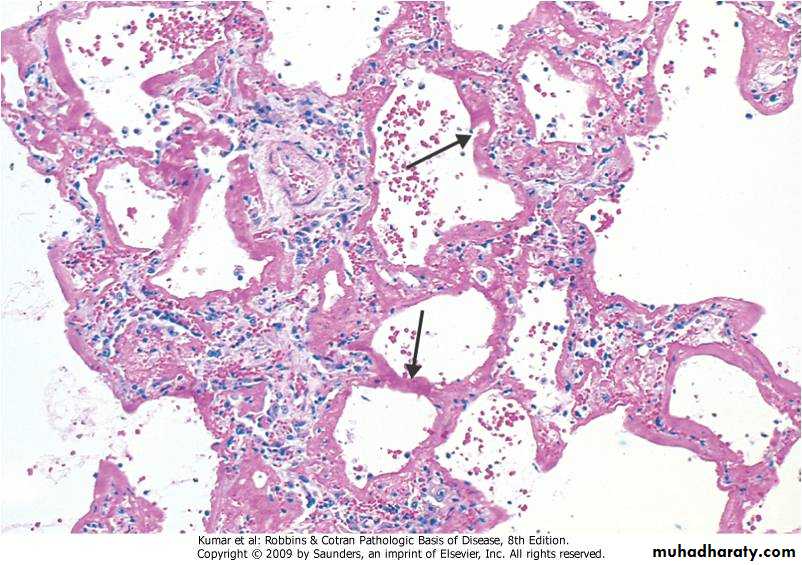

A clinical syndrome caused by diffuse alveolar capillary endothelial and epithelial cell damage.Increased permeability result in exudation of fluid.

Clinically: severe respiratory distress , cyanosis & respiratory failure.

Grossly:

The lung is heavy red congested &edematous

Micro:

Diffuse alveolar wall damage( epithelial & endothelial)

Alveolar wall is lined by hyaline materials Latter on intra alveolar organization takes place

Adult Respiratory Distress Syndrome(ARDS)